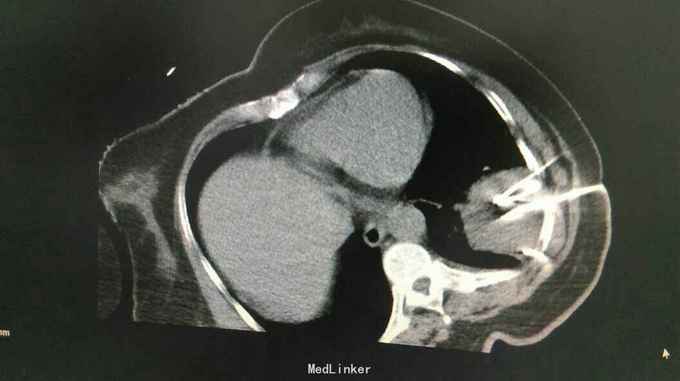

查体:体温:36℃,脉搏:86次/分,呼吸:21次/分,血压:137/81mmHg,胸廓无畸形,两侧对称,双肺呼吸动度一致,左下肺呼吸音减弱,未闻及干湿罗音。心率:86次/分,律齐,心前区及各瓣膜听诊区未闻及杂音,腹软,无压痛及反跳痛。双下肢体无水肿。 辅助检查:胸部CT示:左肺下叶,双肺多发转移灶。于10月16日行左侧胸腔积液穿刺引流,胸水病理检查示:可见少许核异型细胞,考虑为腺癌细胞 颅脑MR检查示:右侧小脑半球两处异常信号,转移瘤可能,右侧放射冠区陈旧性腔梗。

中医诊断: 肺积 正虚瘀结 西医诊断: 1.左肺占位性病变:双肺转移? 2.2型糖尿病 3.冠状动脉粥样硬化性心脏病 治疗经过:,于10月8日下午行左肺占位穿刺活检,病理回报示:不除外细支气管肺泡癌。于10月12日下午行左肺癌碘125粒源植入术,围手术期给予抗感染、支持治疗。于10月16日行左侧胸腔积液穿刺引流,胸水病理检查示:可见少许核异型细胞,考虑为腺癌细胞,给予胸腔药物灌注治疗。于10月25日-29日给予患者生物细胞免疫DC+CIK治疗。 患者家属拒绝静脉化疗,给予口服特罗凯治疗!

患者治疗后一月余行肺ct检查病灶肺部病灶明显缩小!口服特罗凯治疗耙向治疗!